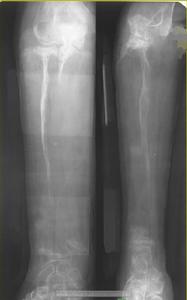

溶骨病的診斷只要是藉助於影像學的表現:大塊骨質溶解,X光上可見骨的大面積的消失,大量纖維化完全或部分替代了骨組織,患者可並發病理性骨折表現。

X線,核磁共振等影像學的檢查,也可輔助做病理學檢查